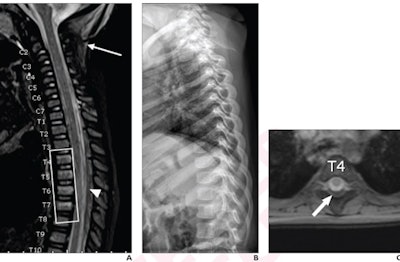

Results showed abusive head trauma was diagnosed in 79 out of 148 (53.4%) children who underwent whole-spine MRI, versus 2 out of 108 (1.9%) who did not undergo whole-spine MRI (p < 0.001). In children who underwent whole-spine MRI, all injuries were observed in the thoracolumbar spine, the authors found.

In addition, major findings (subdural hematoma, epidural hematoma, ligamentous injury, and spine fracture not identified by skeletal survey) were detected in 31.8% of whole-spine MRI examinations. In 51.1% of children with major findings, the major findings were limited to the thoracolumbar spine.